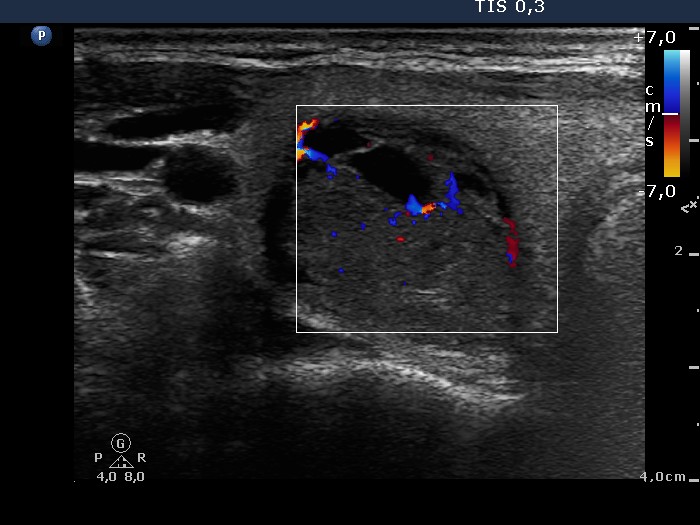

Ultrasonography revealed a moderately hypoechogenic, partly cystic nodule in the right lobe. The nodule displayed perinodular blood flow, while the presence of a halo sign was equivocal. The left lobe was echonormal with a small hypoechogenic lesion.